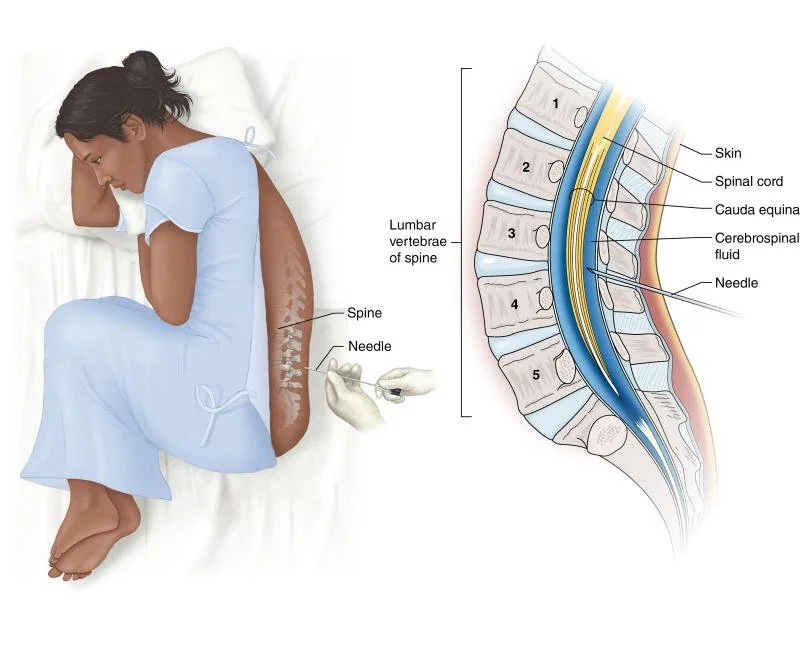

Medical Illustration

All images are works made for hire and are the exclusive property of the client. These are shown as sample purposes of my work only. For licensable work, please see my Illustration Services page.

Medical Illustrator for Precision Graphics, Lachina, and Human Kinetics Publishing (current)

Contract freelancer for many others, some examples of my work below.